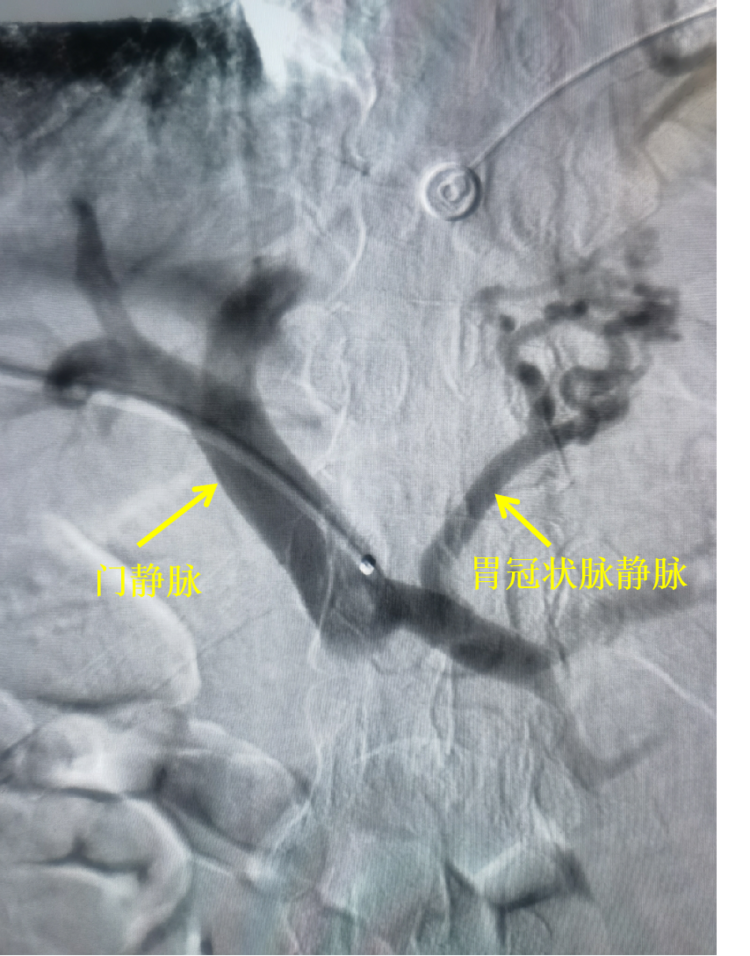

B超引导下经皮穿刺门静脉成功,造影显示:门脉明显增粗、增宽,明确胃冠状静脉走形。

进入胃冠状静脉造影显示:胃冠状静脉明显增粗,食管胃底静脉迂曲、增粗、成团。